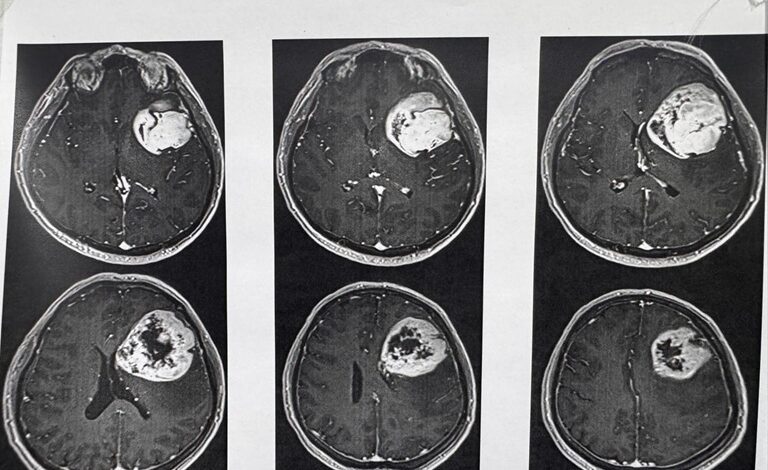

Un hombre de 54 años fue operado con éxito de un tumor cerebral en el Centro Médico “20 de Noviembre” del ISSSTE en la Ciudad de México. La cirugía duró siete horas y se realizó con el paciente despierto para preservar sus habilidades de lenguaje y motricidad. Se utilizaron herramientas avanzadas como un neuronavegador y un microscopio quirúrgico. Los médicos detectaron el tumor maligno a través de tomografías y resonancias magnéticas. Tras la operación, el paciente se recuperó rápidamente y fue dado de alta para continuar su tratamiento en casa. Este caso se suma a otro exitoso procedimiento realizado en julio a una paciente de 34 años. Durante la operación participaron varios especialistas, como un neuroanestesiólogo, una neuropsicóloga, residentes de neurocirugía y anestesia, un psicólogo y enfermeras especializadas. La intervención fue liderada por el neurocirujano Cuauhtémoc Gil Ortiz Mejía.